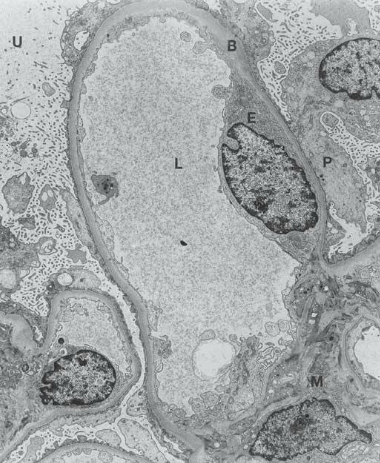

minimal change disease (no abnormality on light microscopy)

finding in minimal change disease on electron micrograph

effacement of foot processes